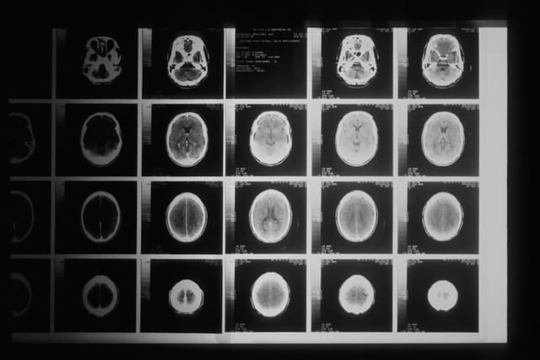

シャイドレーガー症候群は、多系統萎縮症の分類の中の1つ

シャイドレーガー症候群は、多系統萎縮症の分類の中の1つです。多系統萎縮症の約16%の人がシャイドレーガー症候群であると言われています。

発病すると尿失禁や失神などの自律神経障害が起き、発病してから前半期の主な症状が自律神経障害である多系統萎縮症がシャイドレーガー症候群と特別な呼ばれ方で呼ばれているのです。